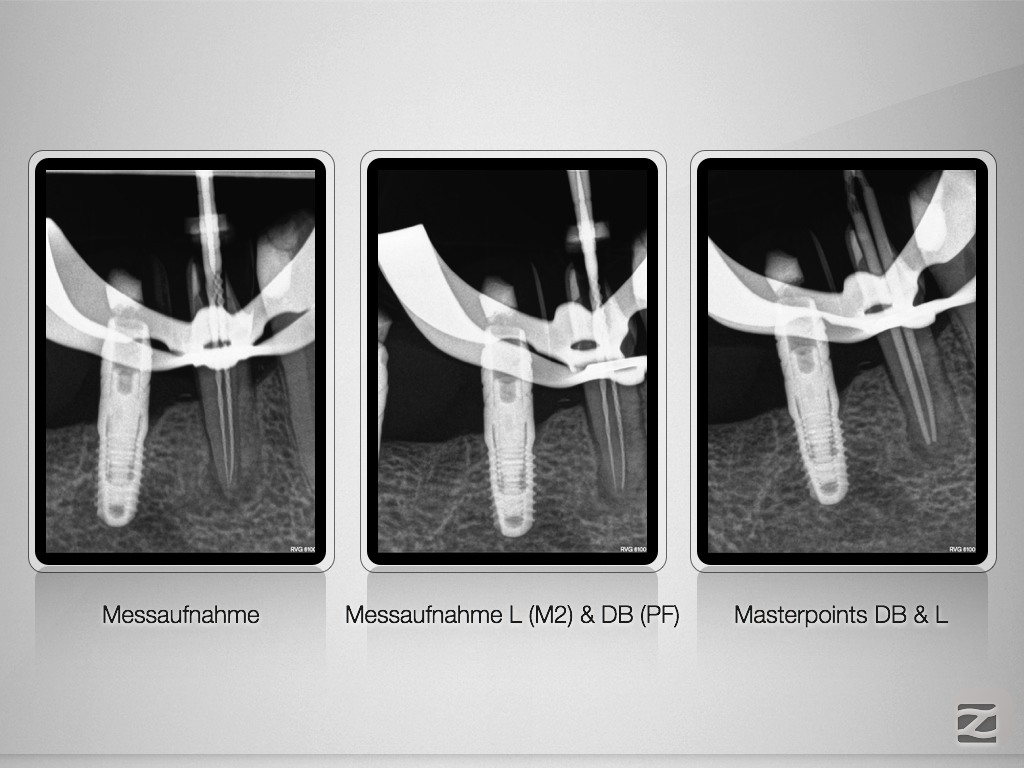

Prämolar mit Hürden